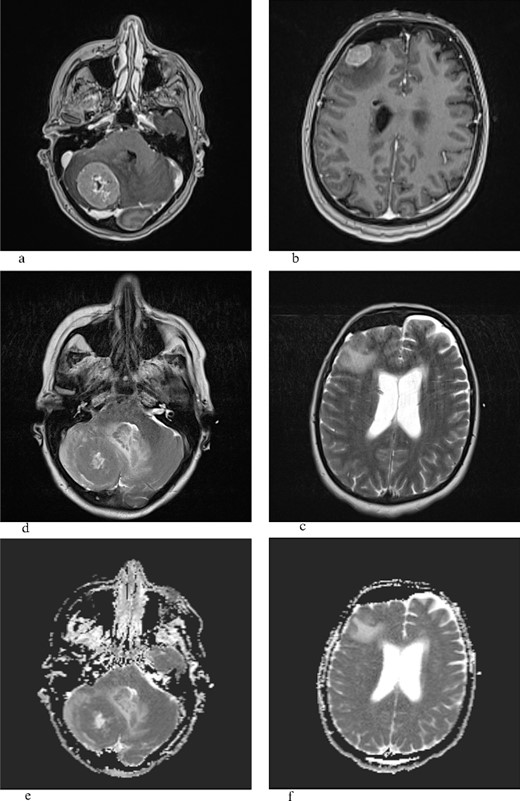

A 40-year-old female presented with confusion, ataxia, and an unsteady gait with a deteriorating Glasgow coma score (GCS). Neuro-radiological evaluation via brain computerized tomography (CT) revealed a hyperdense, postcontrast-enhanced lesion in the right posterior fossa, surrounded by perifocal edema, compressing the fourth ventricle. Another lesion with similar characteristics was noted frontally on the right side, likely secondary. After the fourth ventricle’s compression, the lateral and third ventricles dilated, leading to hydrocephalus. The initial surgical intervention involved right frontal bone trepanation and external ventricular drainage system implantation. After the initial operation, the patient was clinically stable, with GCS 15. She was referred to the brain MRI confirming intracranial secondary changes, revealing lesions in the right cerebellar hemisphere and right frontal cortex, with contrast enhancement on T1W, perifocal edema on T2W, and diffusion restriction on ADC sequence (Fig. 1). Following the MRI scan, further scanning and disease staging investigations were necessary. The CT scan of the thorax, abdomen, and pelvis unveiled an irregularly shaped structure suggestive of a suspicious tumor in the upper lobe’s apicoposterior segment and left lung. The 24 × 18 × 25 mm lesion, inseparable from the pleura over a 10-mm length, exhibited necrotic regions and a solid postcontrast enhancing component. Additionally, enlarged lymph nodes (22 × 18mm) were noticed in the left lower paratracheal mediastinal group, accompanied by notable centrilobular and paraseptal emphysema.

T1W with gadolinium contrast (a,b), T2W (c,d), ADC (e,f): the frontal lesion measures 1.8 × 2.1 cm (transverse plane) and 1.9 × 1.4 cm (coronal plane), while the lesion in the right cerebellar hemisphere measures 3.5 × 2.8 cm (coronal plane) and 3.9 × 3.6 cm (transverse plane), and both lesions show heterogeneous signal intensity, are surrounded by a zone of perifocal edema, and do not demonstrate that central or marginal enhancement with contrast agent in postcontrast imaging, possible necrosis, and ADC sequence shows restricted diffusion.

Lung MEC with BM presents challenges to physicians due to the rarity of the disease and the complexity of the treatment. While it is a common salivary gland carcinoma, it is not often seen as a pulmonary disease, especially with brain metastases [10]. Predilection sites include predominately (53%) parotid, sublingual, and submandibular glands and rarely lung [11]. Macroscopically, they mostly present as fixed, firm, often cystic, and painless tumors with a mucosae overlayer. Histopathologically, it is characterized by mucinous and squamous (epidermoid), and intermediate-type cells. They are usually multicystic with solid components. The low-grade type is characterized by >50% mucinous cells, while the high-grade type is characterized by a predominance of epidermoid cells with <10% [5, 11, 12]. Since it was first described by Smetana et al. [2], not many reports can be found describing radiological characteristics or treatment options. Previous reports expressed difficulties in radiological differentiation from the abscess of the brain [2, 13]. Our MRI brain scan verified infratentorial and supratentorial predilection sites, heterogeneous signal intensity, and the presence of perifocal edema. The difference between the two lesions is in the presence of necrosis, which is found in infratentorial lesions, which corresponds to the previous radiological description of high-grade lung MEC [4, 5, 14]. The low value in the central portion of the infratentorial lesion on the ADC scan confirms the previous report by Saito et al. [13].